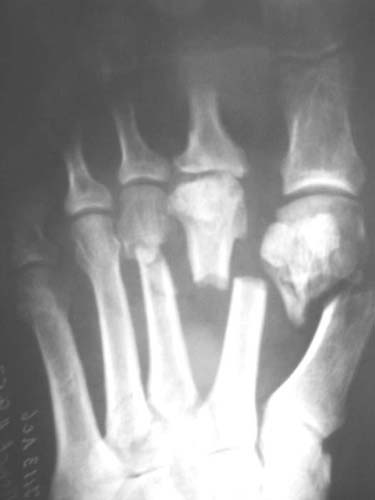

Diagnosis: smash of the front parts of both feet, multiple open fractures of metatarsus bones and phalanxes of toes, contused-scalped wounds.

Left: lacerated-contused wound on the back surface (4*7cm) with smashed edges, wound on the heads of metatarsus II-III bones (4*2cm), contused wound on the sole (2*1cm).

Right foot